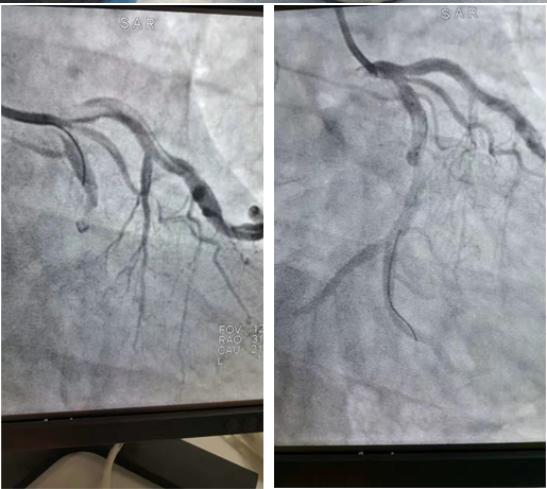

17:00,病人被送入导管室,消毒过程中,患者出现心率和血压下降,心率下降至35bpm,血压65/32mmHg,随后出现多次室速、室颤,情况异常凶险。在心血管疾病中心主任司良毅的主持抢救下,立即予以胸外心脏按压、除颤等治疗后,病人生命体征在药物维持下相对稳定,心率升至61bpm,血压98/50mmHg,17:15完成冠脉造影检查结果提示回旋支近段完全闭塞(左冠优势型,右冠脉先天发育细小),17:20行球囊扩张,回旋支血管可见TIMI2-3级血流,并于回旋支重度狭窄处置入支架,术后血流回旋支血流恢复至TIMI3级,患者胸痛、胸闷症状完全缓解。